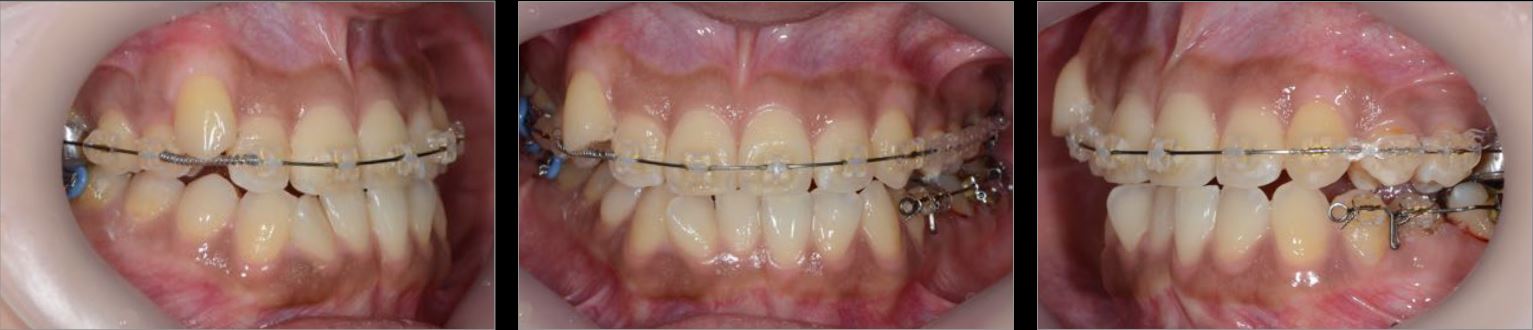

治療中01

治療中02

治療中03

治療中04

治療中05

治療中06

治療期間:3年8ケ月 予後:4年 治療費:¥900,000